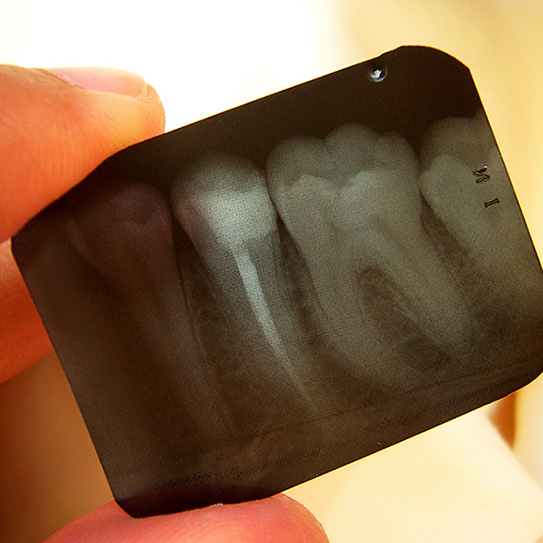

See The Full Picture On Dental X-Rays